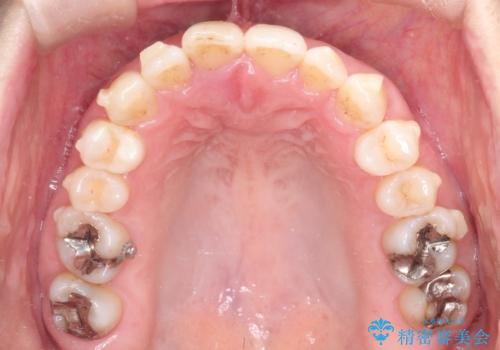

【インビザライン 】前歯のガタガタを治したい

- 前歯のガタガタを主訴に来院されました。

インビザライン で治療しました。途中は使用時間が20時間を切ることもありましたが、それでも頑張って使っていただき1年半で矯正終了することができました。